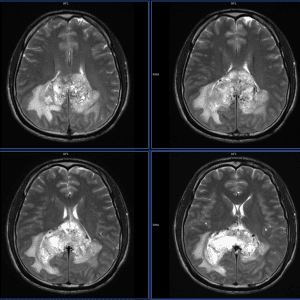

GBM